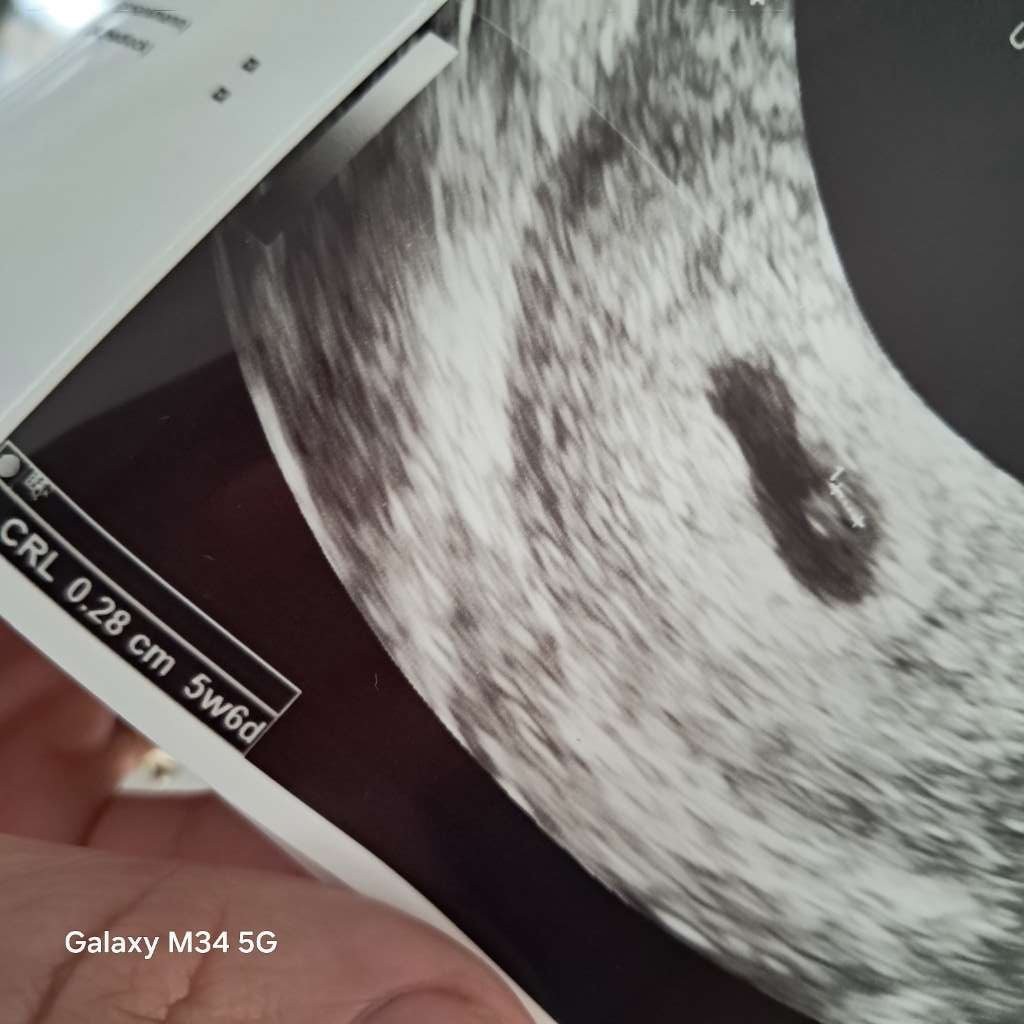

Ja po wizycie mam 0,28cm człowieczka w brzuchu.🥰 Wszystko prawidłowo, zgadza się z moimi wyliczeniami .

• ada9e5bb-6359-4d3d-8ab8-fc568b8426b1.jpeg